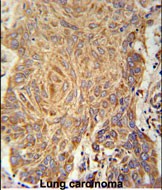

- PCYXL Antibody (C-term) (Cat. #P30702) immunohistochemistry analysis in formalin fixed and paraffin embedded human Lung carcinoma followed by peroxidase conjugation of the secondary antibody and DAB staining. This data demonstrates the use of the PCYXL Antibody (C-term) for immunohistochemistry. Clinical relevance has not been evaluated.